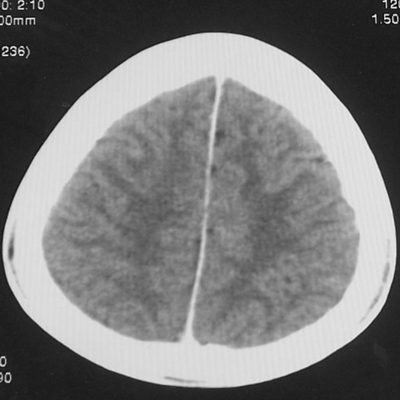

患者、男、18y,头痛5天入院。

左小脑、右丘脑区低密度影,无明显强化及占位表现,男18y,先考虑脑部炎性病变,如脑炎、血行播散性感染等,建议结合临床如脑脊液检验。

单独看左侧小脑半球的不规则形囊性低密度灶,从发病部位、年龄以及无强化、无占位效应的特点可以考虑毛细胞瘤型星形细胞瘤。同样,如果单独看右侧丘脑的近圆形低密度,也可以考虑囊变形星形细胞瘤。只是胶质细胞瘤一般为单发直接浸润、蔓延生长,而不是在脑内同时出现多个病灶,且瘤周没有一点儿水肿,暂时不予以考虑。

同时,现在已经进入冬天,一氧化碳中毒也需要考虑进去。不知道增强是什么时间做的,与平扫间隔几天?如果中间时间比较久而且进行吸氧等治疗,则平扫所示右侧颞叶密度比较低、右侧小脑半球以及脑桥也似有片囊状低密度,但在增强却没有发现就可以比较合理的解释了。